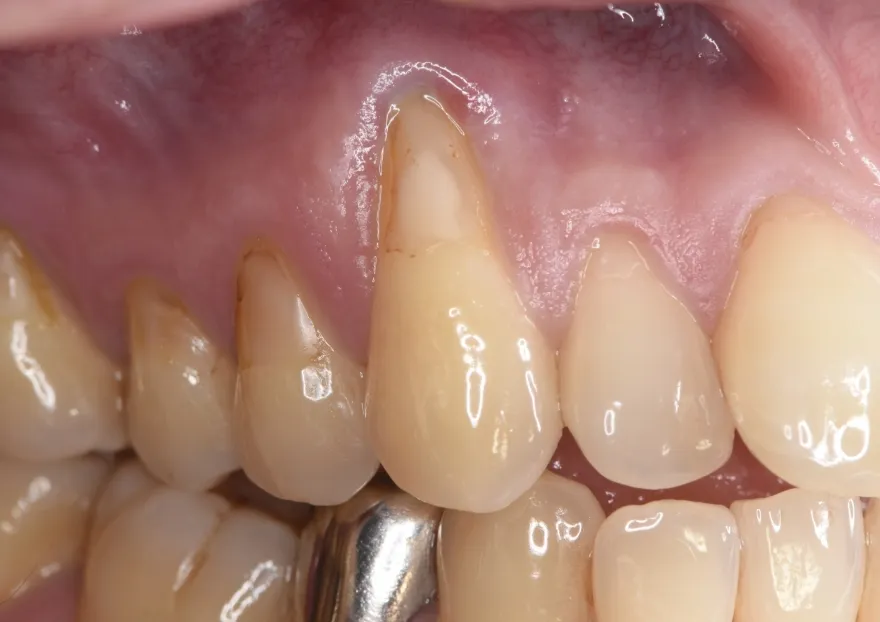

• 術前

• 術後

歯周形成外科は、歯周病治療の一環として行われる外科治療です。歯茎の退縮(下がり)や、凹みの改善など、従来の治療では充分な改善が難しい症例に対して行います。

エムドゲインやリグロスといった歯周組織再生材料を併用し、最新の治療技術と繊細な手術手法により、歯肉の厚みを増やすことで更なる退縮を予防することを目的とします。また、失われた歯周組織を可能な限り再生・修復させることで、見た目の改善だけでなく、清掃性の高い口腔環境を作り長期的なお口の健康を目指します。